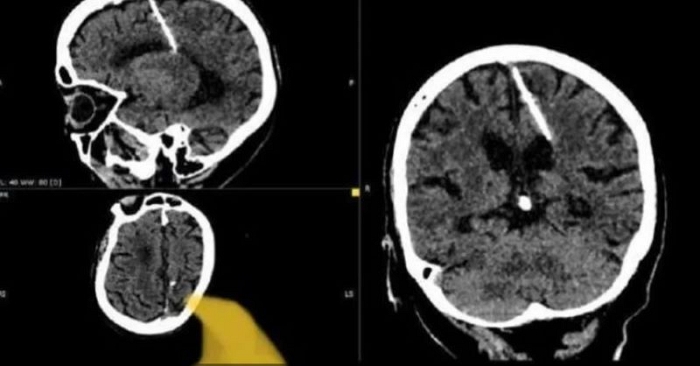

الإبرة اخترقت الفص الجداري الأيسر للدماغ

عثر أطباء روس خلال فحص بالتصوير المقطعي على إبرة بطول ثلاثة سنتيمترات موجودة منذ ثمانين عامًا داخل دماغ امرأة مسنّة في أقصى الشرق الروسي.

ونوّهت الى ان الإبرة اخترقت الفص الجداري الأيسر، لكن لم يكن لها التأثير المقصود، إذ نجت الفتاة، فيما لم تَشكُ قط من الصداع بسبب وجود الإبرة في دماغها طوال هذه السنوات، ولم تكن تواجه أي خطر، لافتة إلى أن "حالتها، حاليًا، تحت مراقبة الطبيب المعالج" وإنهم لن يحاولوا "إزالة الإبرة خشية أن يفاقم ذلك حالتها".